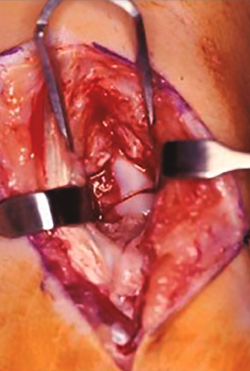

Se comienza la artroscopia en la articulación radiocarpiana a través del portal 3/4 con la colocación de la óptica para realizar un recorrido articular con el fin de identificar la existencia de lesiones asociadas o valorar fracturas del polo proximal del escafoides (Figura 8).

Figura 8. Visualización de la fractura de escafoides desde el portal 6R.